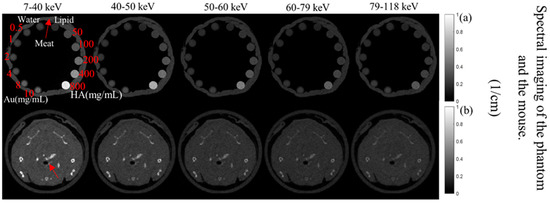

3.1. Phantom Imaging

3.2. Mouse Imaging